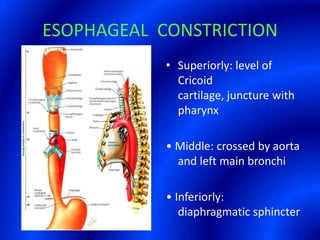

This document provides information about a barium swallow procedure. It begins with an introduction and overview of the embryology and anatomy of the pharynx and esophagus. It then describes the procedure itself, including preparation, technique, views obtained, and indications. Specific conditions that may be examined include pharyngeal and esophageal webs, foreign body impaction, scleroderma, dysphagia, mediastinal masses, and carcinoma. Diagrams are provided to illustrate normal anatomy and various pathological findings.